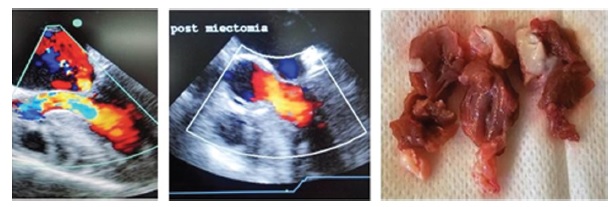

Resultados: Edad promedio 53,3 ± 13,4 años. La mortalidad perioperatoria (< 30 días) fue del 0%. Un paciente falleció a los 90 días (3,5%). No se produjeron comunicaciones interventriculares, daño de la válvula aórtica ni se reemplazó la válvula mitral en ningún paciente. El 91% de ellos se encontraban con disnea en CF III-IV en el preoperatorio, los restantes tenían angina o síncope. En el seguimiento, el 92,8% estaban asintomáticos, 1 paciente en CF III y otro en CF II. El gradiente preoperatorio basal promedio fue de 53,5 mmHg y con valsalva 86,4 mmHg; los gradientes basal y con valsalva posoperatorios fueron 9,4 mmHg y 13,5 mmHg (p < 0,01). Al seguimiento, los gradientes en reposo y con valsalva fueron aún más bajos, 8,3 mmHg y 10,7 mmHg, respectivamente (p: NS). Nueve pacientes (32%) presentaban insuficiencia mitral moderada a grave previa por movimiento anterior sistólico o patología intrínseca mitral. Se detectó solo un paciente con insuficiencia mitral moderada asintomática en el seguimiento (3,5%).La mediana de seguimiento fue de 400 días, Pc 25-75 de 695 días(mínimo de 30 días y el máximo de 1868 días).

Conclusión: Con la miectomía septal ampliada se obtiene una mejoría hemodinámica y clínica de los pacientes sintomáticos,con bajo número de complicaciones posoperatorias. Esto tiene como resultado una mejor calidad de vida.